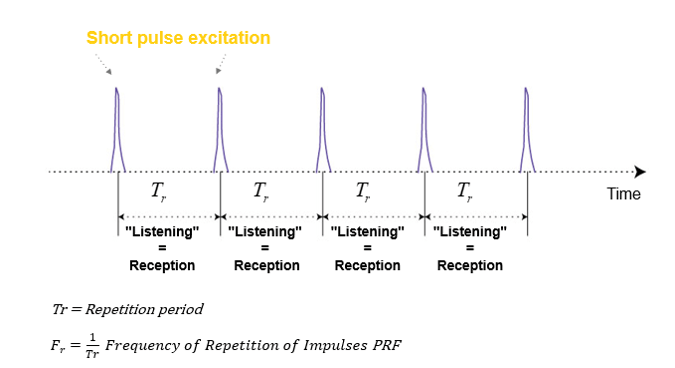

What is Pulse Repetition Frequency? And what does it depend on?

Pulse Repetition Frequency (PRF) is the number of ultrasound pulses emitted by the transducer per second. It depends on the speed of sound and the depth of exploration; Thus it can be altered by changing the depth of imaging. The further the ultrasound travels into the tissue, the higher the PRF becomes.